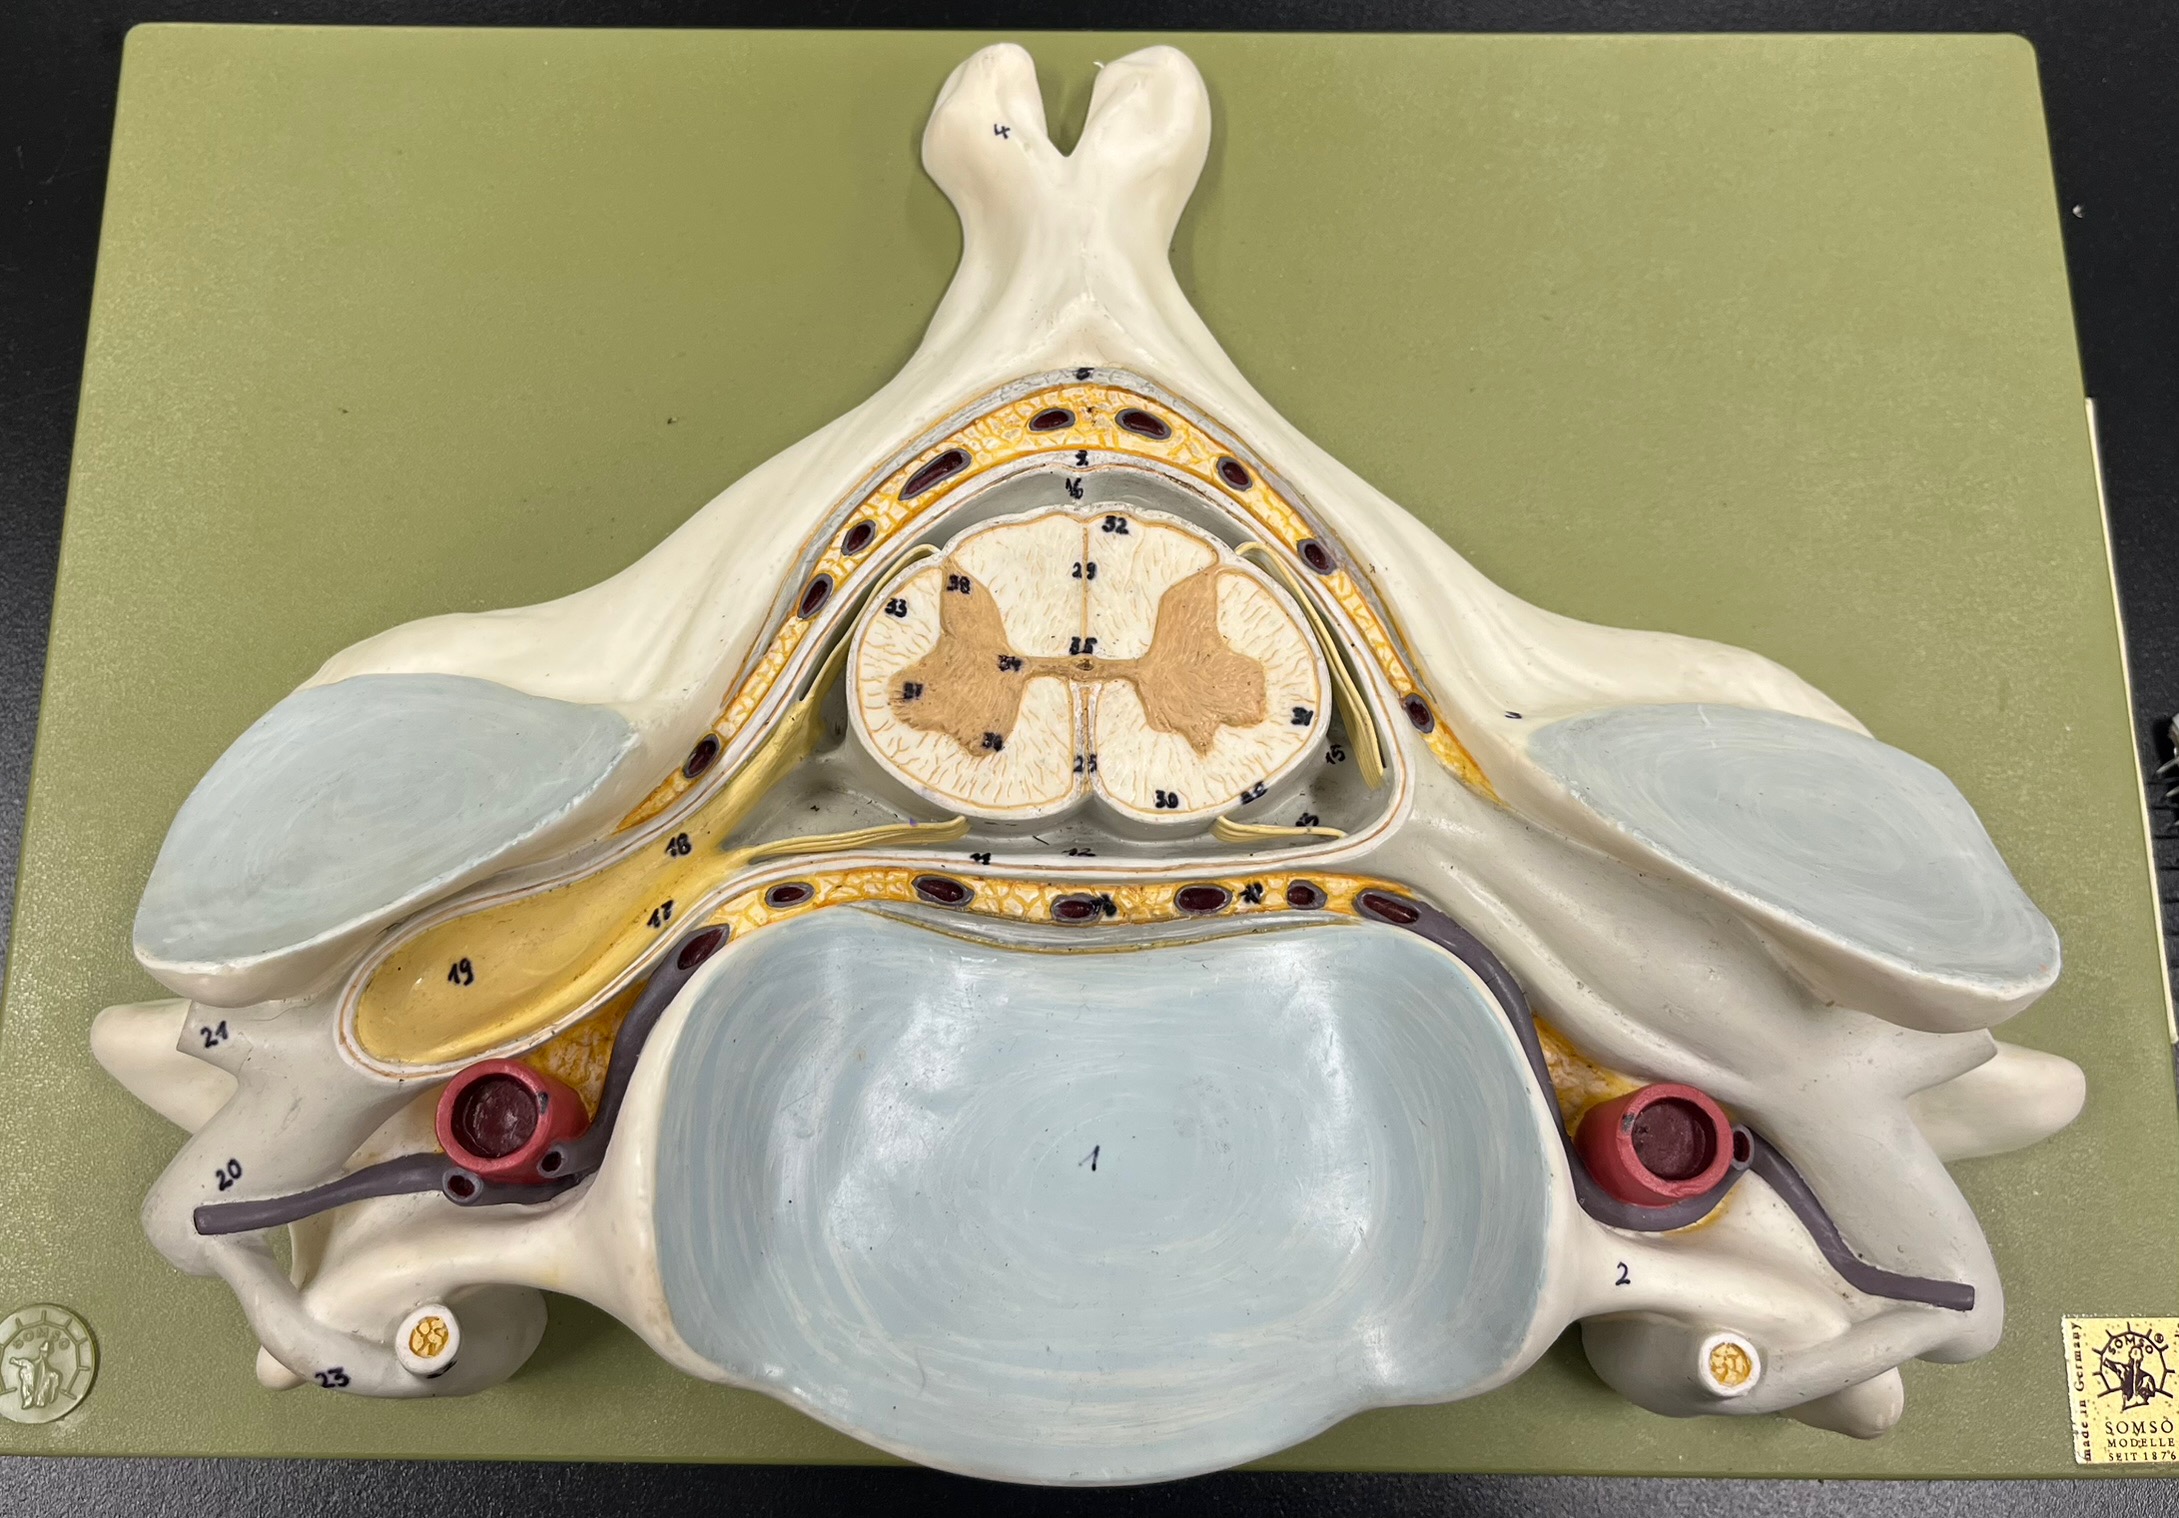

epidural space

dura mater

subdural space

arachnoid mater

subarachnoid space

pia mater

denticulate ligaments

What is the groove here?

anterior median fissure

posterior median sulcus

posterior (dorsal) horn

posterior (dorsal) horn; R—>L

anterior (ventral) horn

lateral horn (selected models)

gray commissure

central canal

anterior column

lateral column

posterior column

white commissure

posterior (dorsal) root ganglion

What is the bulb here?

posterior (dorsal) root ganglion

posterior (dorsal) root

posterior (dorsal) root

anterior (ventral) root

anterior (ventral) root

dorsal ramus

dorsal ramus

ventral ramus

ventral ramus

rami communicantes

rami communicantes

sympathetic chain ganglia

sympathetic chain ganglia